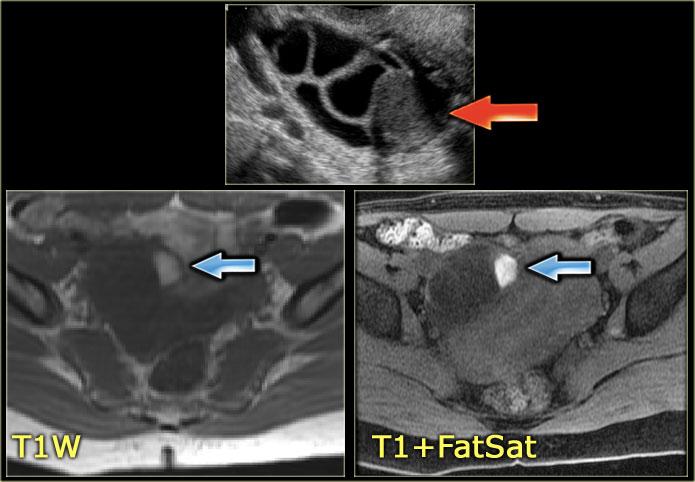

Chụp MRI là phương tiện bổ sung có giá trị cho siêu âm, vì cho phép nhận diện các sản phẩm của máu trong các khối xuất huyết — những khối này có thể bắt chước hình ảnh khối u đặc trên siêu âm.

Hình ảnh MRI chuỗi xung T1W kèm kỹ thuật xóa mỡ có thể phát hiện lượng nhỏ thành phần mỡ, từ đó cho phép chẩn đoán u quái trưởng thành (‘dermoid’).

Chụp MRI chuỗi xung T1W sau tiêm thuốc tương phản từ thể hiện các đặc điểm ác tính như các nốt thành ngấm thuốc và/hoặc các vùng đặc ngấm thuốc có hoặc không kèm hoại tử (3).Các hình ảnh MRI này cho thấy một tổn thương tăng tín hiệu trên chuỗi xung T1W.

Điều này có nghĩa là chúng ta đang đối diện với một tổn thương chứa mỡ, tức là u quái dạng nang trưởng thành.Hình ảnh siêu âm cho thấy một tổn thương tăng âm.

Tổn thương tương ứng có tín hiệu cao trên hình ảnh MRI chuỗi xung T1W.

Điều này gợi ý thành phần máu, protein nồng độ cao hoặc mỡ.

Trên hình ảnh kèm kỹ thuật xóa mỡ, tín hiệu không bị triệt tiêu.

Điều này có nghĩa là chúng ta đang đối diện với một tổn thương chứa máu, nhiều khả năng là nang xuất huyết.